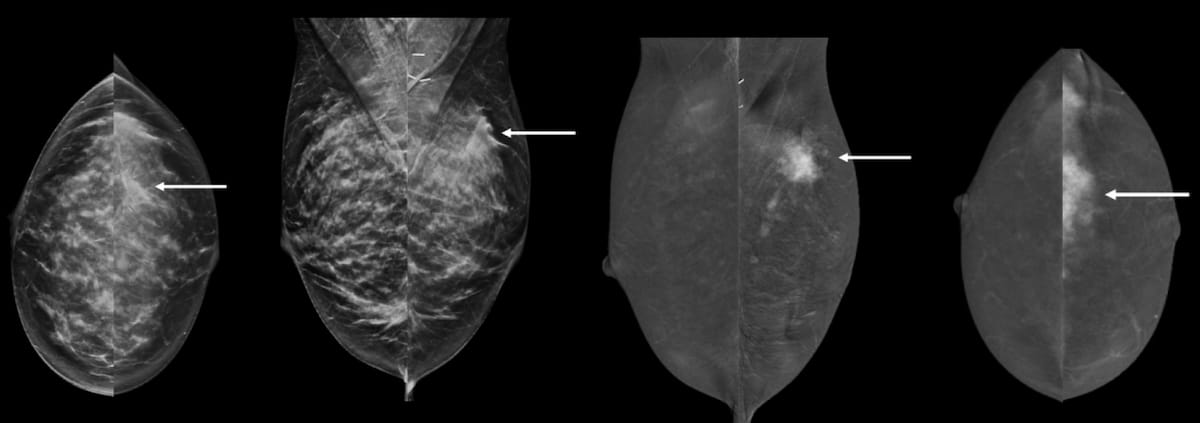

Noting that technique issues, patient positioning miscues and atypical features can all contribute to faulty interpretation with contrast-enhanced mammography (CEM), researchers at the European Congress of Radiology shared their insights on navigating artifacts and limitations with CEM.